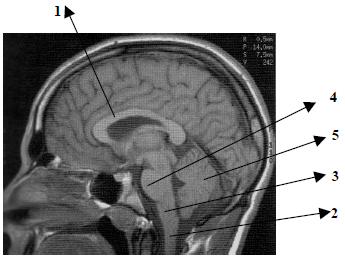

Observe atentamente o corte sagital apresentado na imagem abaixo e assinale a alternativa que apresenta a identificação correta das estruturas assinaladas.

1- medula espinhal, 2- bulbo, 3- ponte, 4- corpo caloso, e 5- cerebelo.

1- corpo caloso, 2- ponte, 3- bulbo, 4- medula espinhal, e 5- cerebelo.

1- bulbo, 2- medula espinhal, 3- cerebelo, 4- ponte, e 5- corpo caloso.

1- corpo caloso, 2- medula espinhal, 3- bulbo, 4- ponte, e 5- cerebelo.